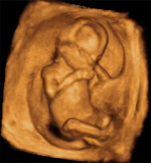

Si hasta ahora lo importante era que los órganos del bebé se formaran correctamente, a partir de la semana 16 de embarazo el desarrollo del feto se centra en una misión importantísima: crecer y crecer. Ahora el niño mide alrededor de 11 centímetros desde la coronilla hasta el coxis y pesa entre 80 y 100 gramos. Y no para de moverse dentro del aún espacioso útero materno.

? El feto es ahora mucho más activo: mueve sin trabas piernas y brazos, lo que quiere decir que su sistema muscular está más evolucionado. Son movimientos que se pueden ver a través de la ecografía. Tú, sobre todo si es tu primer bebé, no los notarás aún. Tendrás que esperar unas pocas semanas para notar esas primeras pataditas. De todas formas, siguen siendo movimientos involuntarios, aunque el sistema nervioso empieza a funcionar y el cerebro controla algunos movimientos.

? Su cabeza ya está bastante erguida. Aunque los párpados siguen cerrados el globo ocular se mueve y en la ecografía es posible distinguir el cristalino. Su piel sigue siendo muy fina y empiezan a formarse el sentido del tacto. Este es el más madrugador, aparte de ser el más extenso, dado que abarca todo su cuerpo.

? En las yemas de los dedos de la mano aparecen el boceto de espirales y arrugas que se convertirán en las huellas digitales. Y en los pies empiezan a crecerle las uñas de los dedos.